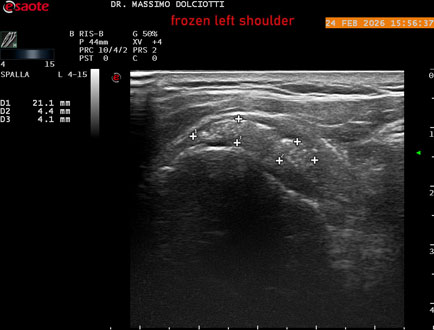

Data inserimento: 02/03/2026

Ecografia del: 24/02/2026

Strumento: Esaote MyLab Eight

Sonda: Lineare Multifrequenza 4-15 MHz

Età Paziente: F 71 anni

Motivazione dell'esame: da 1 mese dolore alla spalla sinistra, anche di notte.

Commento all'esame: le immagini ed il video documentano il tendine sovraspinato sinistro spiccatamente disomogeneo, per presenza di immagine iperecogena, delle dimensioni di 21 x 4 mm, da ricondurre a estesa calcificazione. Quadro clinico di spalla congelata.

Conclusioni: spalla sinistra congelata (frozen left shoulder).

In collaborazione: Dr.ssa Marica Manfredi - Ancona, Dr. Ilir Qose - Ancona

Presentazione: Dr. Massimo Dolciotti - Ancona

Elaborazione digitale: Andrea Dini - Ancona